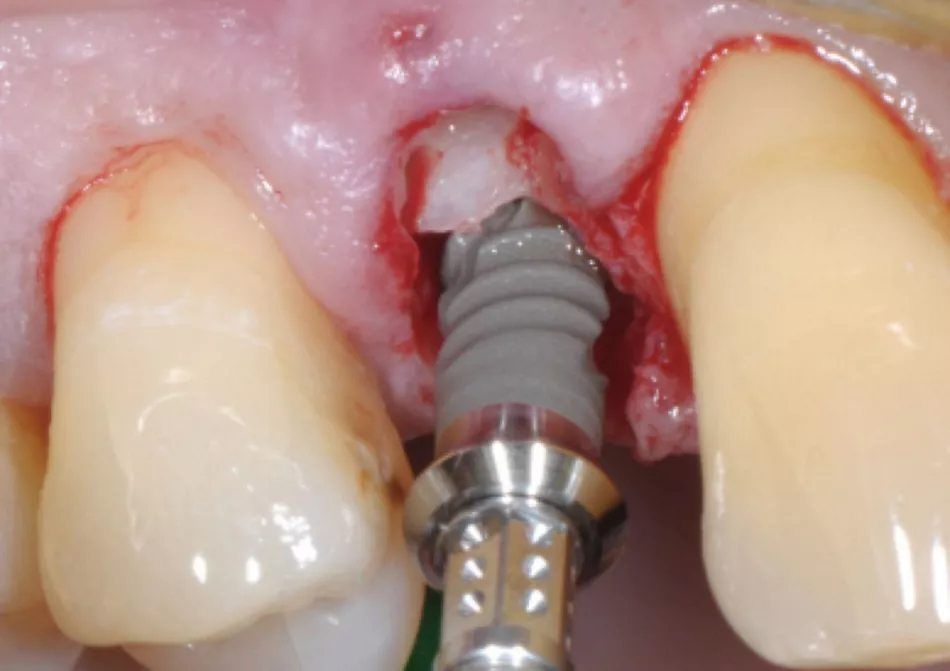

Fig. 4: Straumann® BLT implants are being used for this full arch case with fully guided surgery and immediate temporary loading

(picture courtesy of Dr Nikolay Makarov, see full case report here).